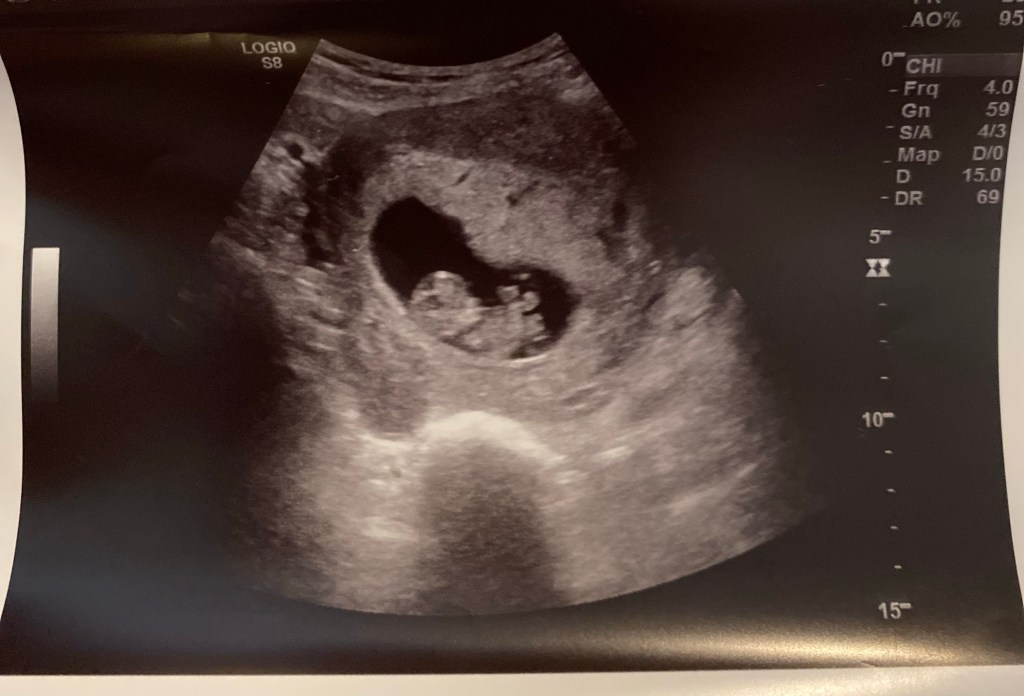

I tried to ride these waves with thoughts of the incredible love and joy I know will my fill my heart the minute I hold that new person or the fact that no life is an accident and that God has a plan for this one. It wasn’t until our first ultrasound when all those thoughts transferred from my head to heart:

As soon I saw that little individual so contentedly squirming and dancing in its first cradle and saw the strong heartbeat all regrets vanished: the ones about finally having my body back and now letting it go again; the ones about my mood swings finally leveling off only to begin again; the ones about our small house getting smaller or our mobility being restricted by a fatigued mama and a newborn’s schedule. The regrets vanished but I have a lingering personal connection with the ongoing debate about the value of human life inside the womb.